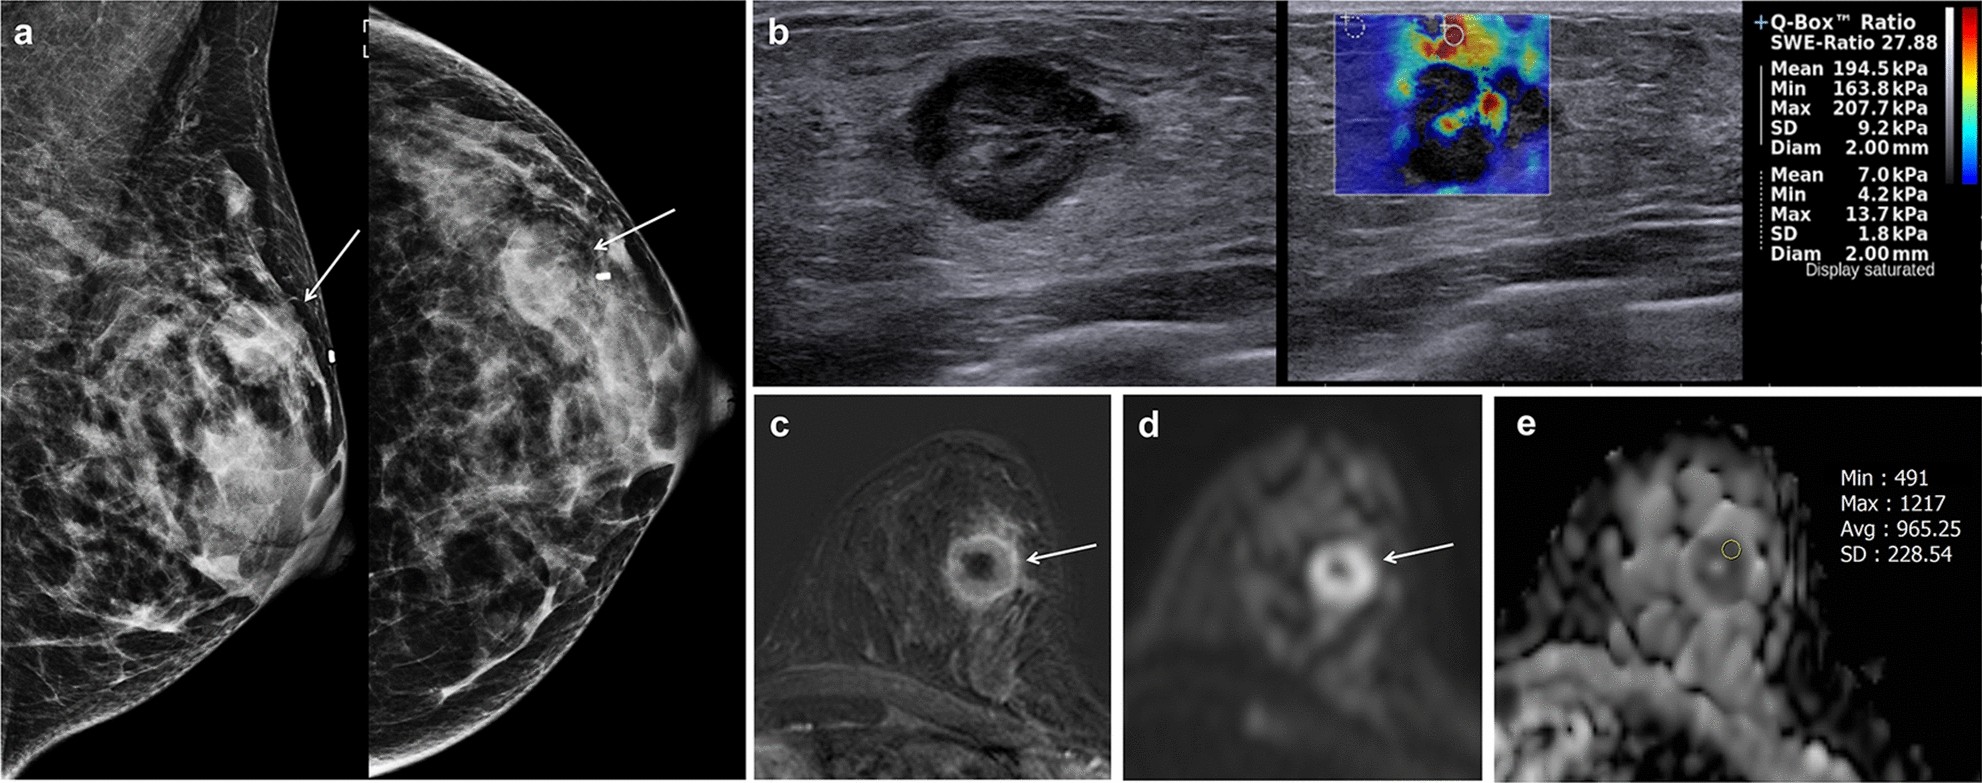

Figure 3

Imaging findings of triple-negative invasive breast cancer of no special type in the left breast of a 67-year-old woman. (a) Images obtained with mammography in the left mediolateral oblique (left) and left craniocaudal view (right) shows an irregular hyperdense mass (arrows) in the upper outer breast. (b) B-mode ultrasound image (left) shows a 22-mm microlobulated heterogenous mass with posterior enhancement. Shear-wave elastography (SWE, right) values are measured, with a mean elasticity of 194.5 kPa and a maximum elasticity of 207.7 kPa. (c) Axial contrast-enhanced T1-weighted subtraction magnetic resonance imaging (MRI) shows a round mass with rim enhancement (arrow). The mass shows early rapid and delayed washout enhancement. (d) Axial diffusion-weighted MRI (b value, 1000 s/mm2) demonstrates a mass with high signal intensity (arrow). (e) On the reconstructed apparent diffusion coefficient (ADC) map, the ADC value of the mass is 0.965 × 10−3 cm2/s. US-guided core-needle biopsy revealed invasive breast cancer of no special type that was estrogen receptor negative, progesterone receptor negative, and human epidermal growth factor receptor 2 negative.